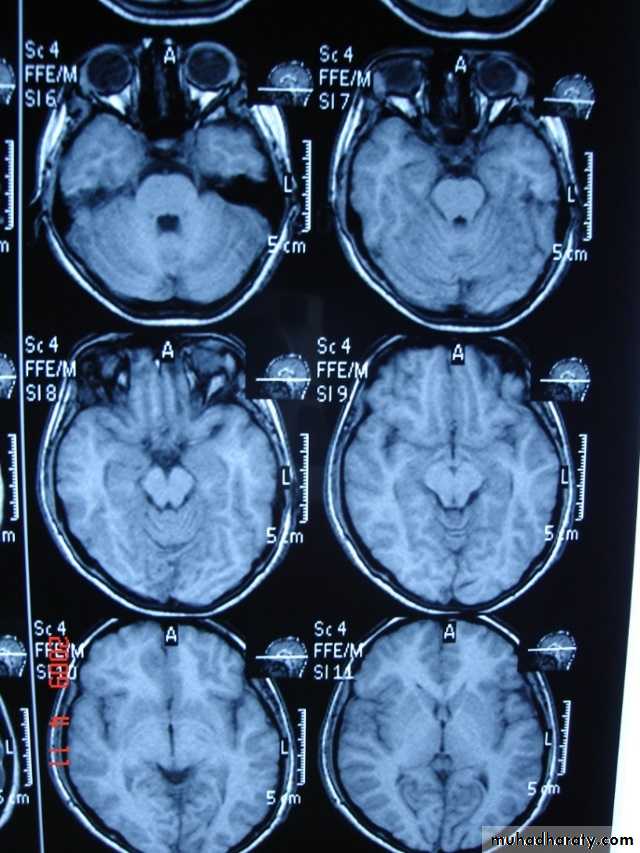

-MRI is more sensitive than CT in the demonstration of MS plaques.

- the most characteristic appearance is that of peri ventricular nodular Hyper intense lesions on T2 weighted images.

-the plaques are also well seen at the gray- white matter interfaces.

-MRI can even image lesions in the spinal cord , brainstem & cerebellum.

-contrast enhancement after giving gadolinium occurs in the acute phase indicating activity & in the chronic phase doesn't enhance.

SAGITAL FLUID ATTENUATION INVERSION RECOVERY SEQUENCE: OVOID PLAQUES ( HIGH SIGNAL INTENSITY) , WHICH ARE PERPENDICULAR TO LATERAL VENTRICLE.